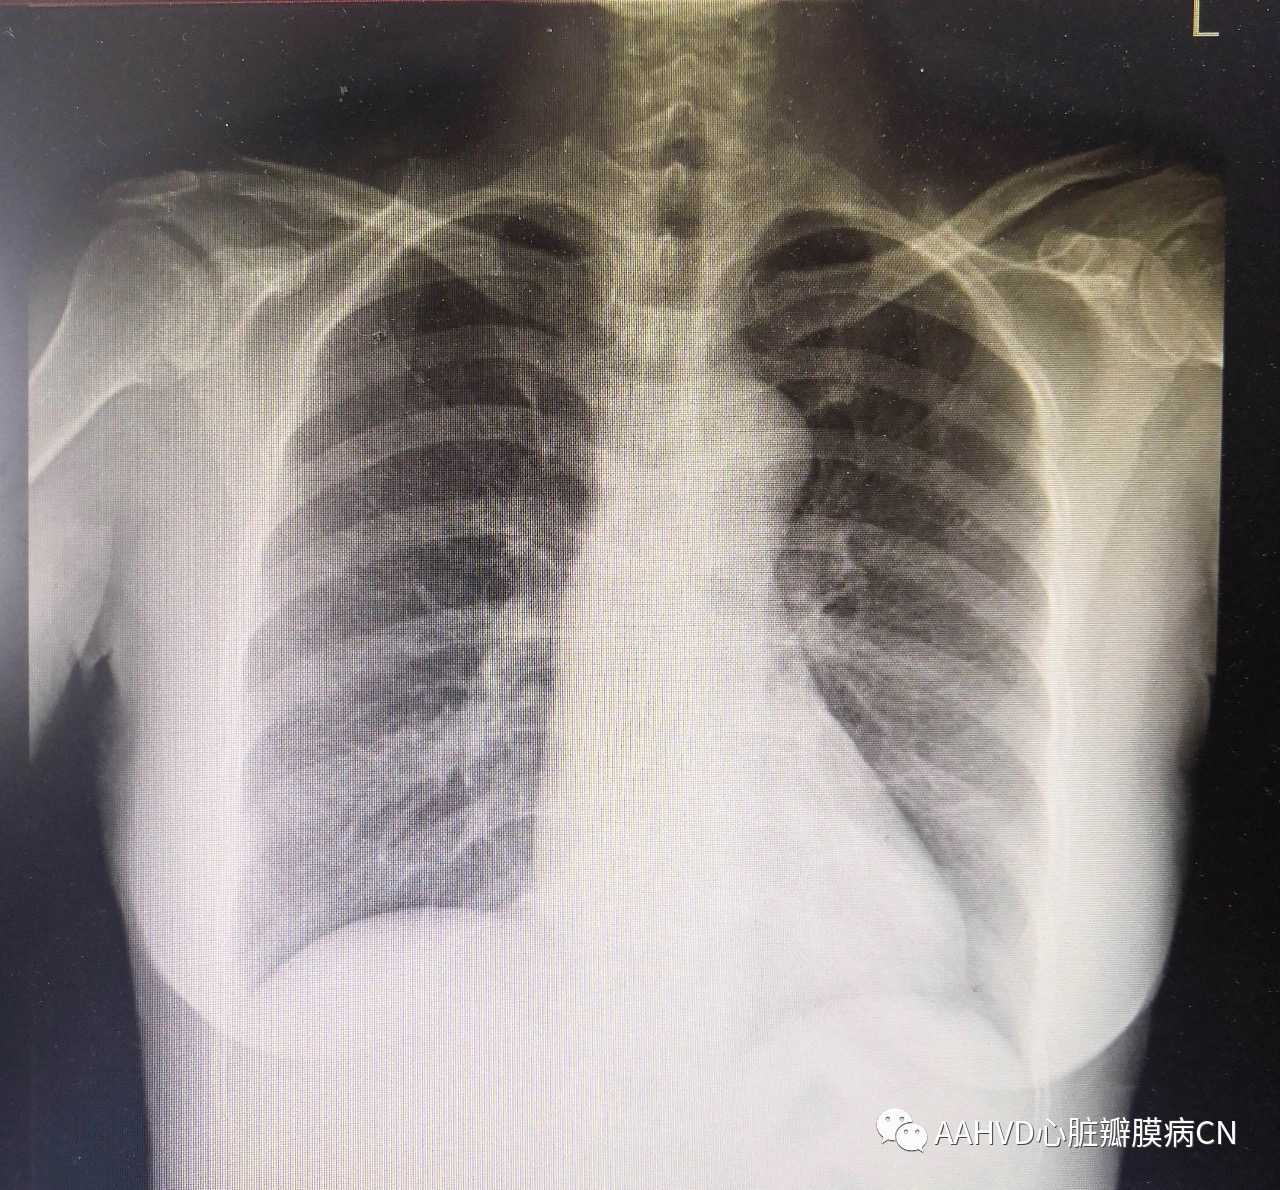

术前胸片

术前经胸超声报告:

二尖瓣前后叶瓣尖增厚,轻度钙化,交界粘连,瓣口面积1.7cm²(轻度狭窄),收缩期二尖瓣偏心性返流,延后叶走行,返流面积6.0cm²(中度返流);舒张期主动脉瓣下少+量返流(轻+度关闭不全);三尖瓣重度返流。